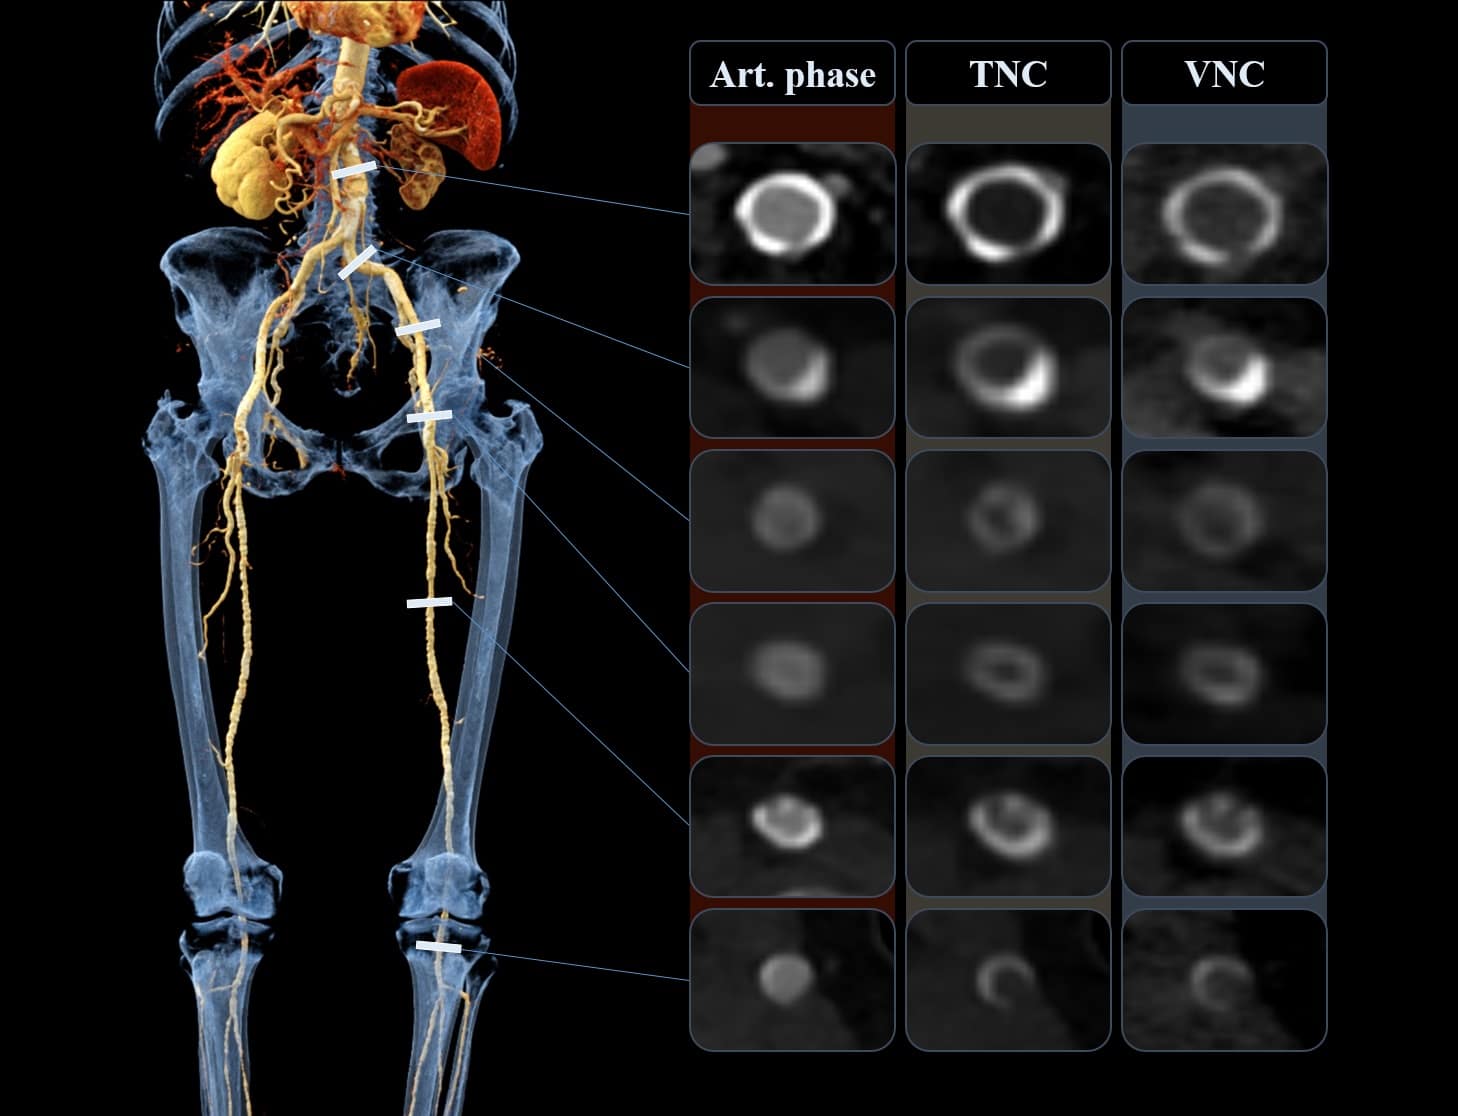

Új CT-technológia segíthet csökkenteni a sugárterhelést az érszűkületes betegek vizsgálatában

Az alsó végtagi érszűkület világszerte több mint 200 millió embert érint. A betegség során a verőerek/artériák beszűkülnek vagy elzáródnak, ami súlyos esetben akár végtagamputációhoz is vezethet. A pontos diagnózis és a kezelés megtervezése érdekében az egyik legfontosabb vizsgálati módszer a CT angiográfia, amely részletes képet ad az erekről. A hagyományos vizsgálat során két felvétel készül: egy kontrasztanyag nélküli (úgynevezett natív), valamint egy kontrasztanyagos sorozat. Ez viszont a beteg számára nagyobb sugárterhelést jelent.

A Semmelweis Egyetem Városmajori Szív- és Érsebészeti Klinikáján elérhető legújabb, kettős energiájú CT készülék azonban képes a kontrasztanyagos felvételekből számítógépes feldolgozással „eltüntetni” a kontrasztanyag hatását, és így létrehozni egy úgynevezett virtuális nem-kontrasztanyagos képet (VNC). Ez a módszer lehetővé teszi, hogy a hagyományos natív felvételre ne legyen szükség, így a beteget kevesebb sugárzás érje. Kutatásunkban azt vizsgáltuk, hogy ezek a virtuális felvételek mennyire közelítik meg a valódi, natív képek minőségét. Eredményeink azt mutatják, hogy a VNC képek ugyanolyan megbízhatóan használhatók a diagnózis felállításában, miközben akár 37 százalékkal csökkenthető a sugárterhelés. Ez az új technológia hozzájárulhat a modern, betegbarát képalkotás fejlődéséhez, és hosszú távon a rutinvizsgálatokban is helyet kaphat – írta összefoglalójában dr. Szablics Fanni és dr. Bérczi Ákos.

Virtual Non-Contrast Reconstructions Derived from Dual-Energy CTA Scans in Peripheral Arterial Disease: Comparison with True Non-Contrast Images and Impact on Radiation Dose

J. Clin. Med. 2025, 14(15), 5571. https://doi.org/10.3390/jcm14155571